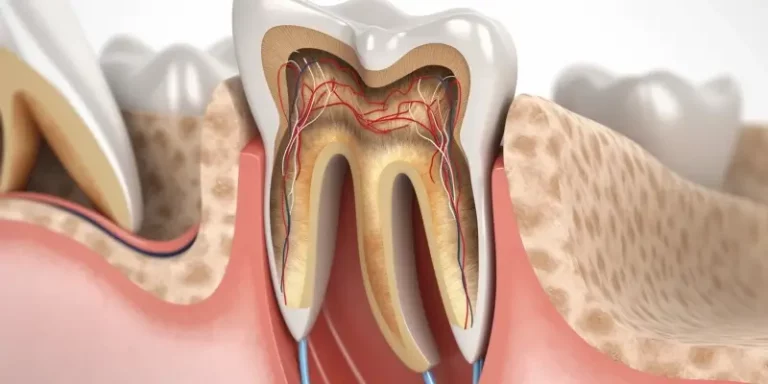

Czas trwania leczenia kanałowego zęba w gabinecie stomatologicznym jest zróżnicowany i zależy od wielu czynników. Najczęściej procedura ta wymaga jednej…

Leczenie kanałowe, znane również jako endodoncja, budzi wiele obaw i często jest kojarzone z silnym bólem. Ta powszechna opinia wynika…

Leczenie kanałowe zęba szóstego, choć często kojarzone z jednym zabiegiem, w rzeczywistości jest procesem, którego czas trwania może być bardzo…

Leczenie kanałowe, znane również jako endodontyczne, jest procedurą stomatologiczną mającą na celu usunięcie zainfekowanej lub uszkodzonej miazgi zębowej, oczyszczenie i…

Pytanie o bezpieczeństwo leczenia kanałowego jest jednym z najczęściej zadawanych przez pacjentów, którzy stają przed koniecznością podjęcia tej procedury. Strach…

Decyzja o poddaniu się leczeniu kanałowemu, znanemu również jako endodoncja, jest często podejmowana w sytuacjach, gdy ząb uległ znacznemu uszkodzeniu…

Decyzja o wyborze między plombą a leczeniem kanałowym jest kluczowa dla zdrowia naszego uzębienia i komfortu życia. Oba zabiegi mają…